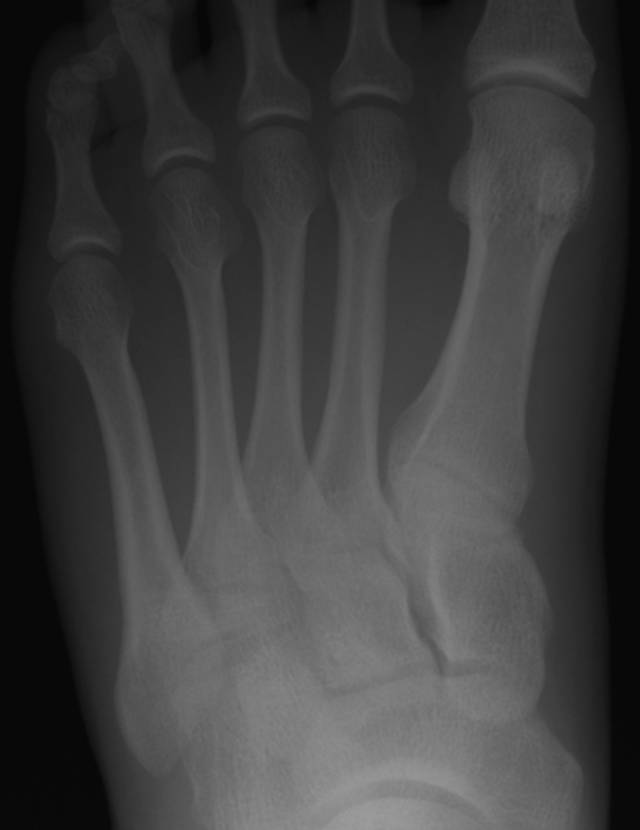

图2A-19岁男性运动损伤后。A,初始斜位放射照片显示不完全的第二和第三跖骨轴骨折。

图 2B-19岁男性运动损伤后。B,1周后在没有放射技术人员的门诊办公室获得的随访X光照片不显示跖骨骨折,因为穿透不足和不正确的管成角。注意缺乏小梁骨细节和跖骨和导管骨关节的可视性差。